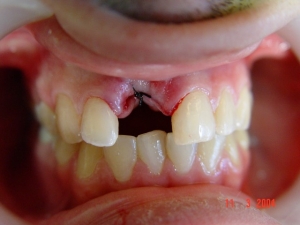

בחור צעיר, הגיע עם שן שבורה כתוצאה מתאונה. הוחלט לעקור את השן ולבצע שתל ושיקום

בוצעה עקירת השן